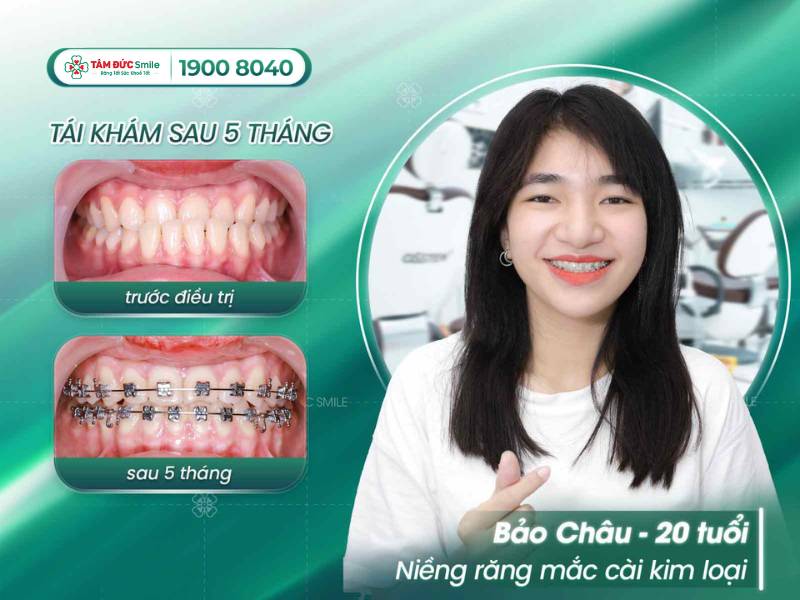

1.1.3. Khách hàng niềng răng ở Tâm Đức Smile

Nha khoa Tâm Đức Smile đã khẳng định được uy tín và chất lượng niềng răng qua 11 năm hoạt động, phát triển mạnh mẽ. Mỗi năm, nha khoa giúp hàng ngàn khách tại Đà Nẵng và các khu vực lân cận lấy lại nụ cười tự tin, rạng rỡ.

Khách hàng hài lòng với trải nghiệm niềng răng tại nha khoa Tâm Đức Smile

2. Khách hàng nói gì sau khi niềng răng tại hệ thống nha khoa Tâm Đức Smile?

Phản hồi của khách hàng là yếu tố quan trọng nhất, phản ánh chất lượng dịch vụ tại địa chỉ niềng răng ở Đà Nẵng Tâm Đức Smile. Bạn có thể xem nội dung đánh giá dịch vụ trên hệ thống Website của nha khoa.